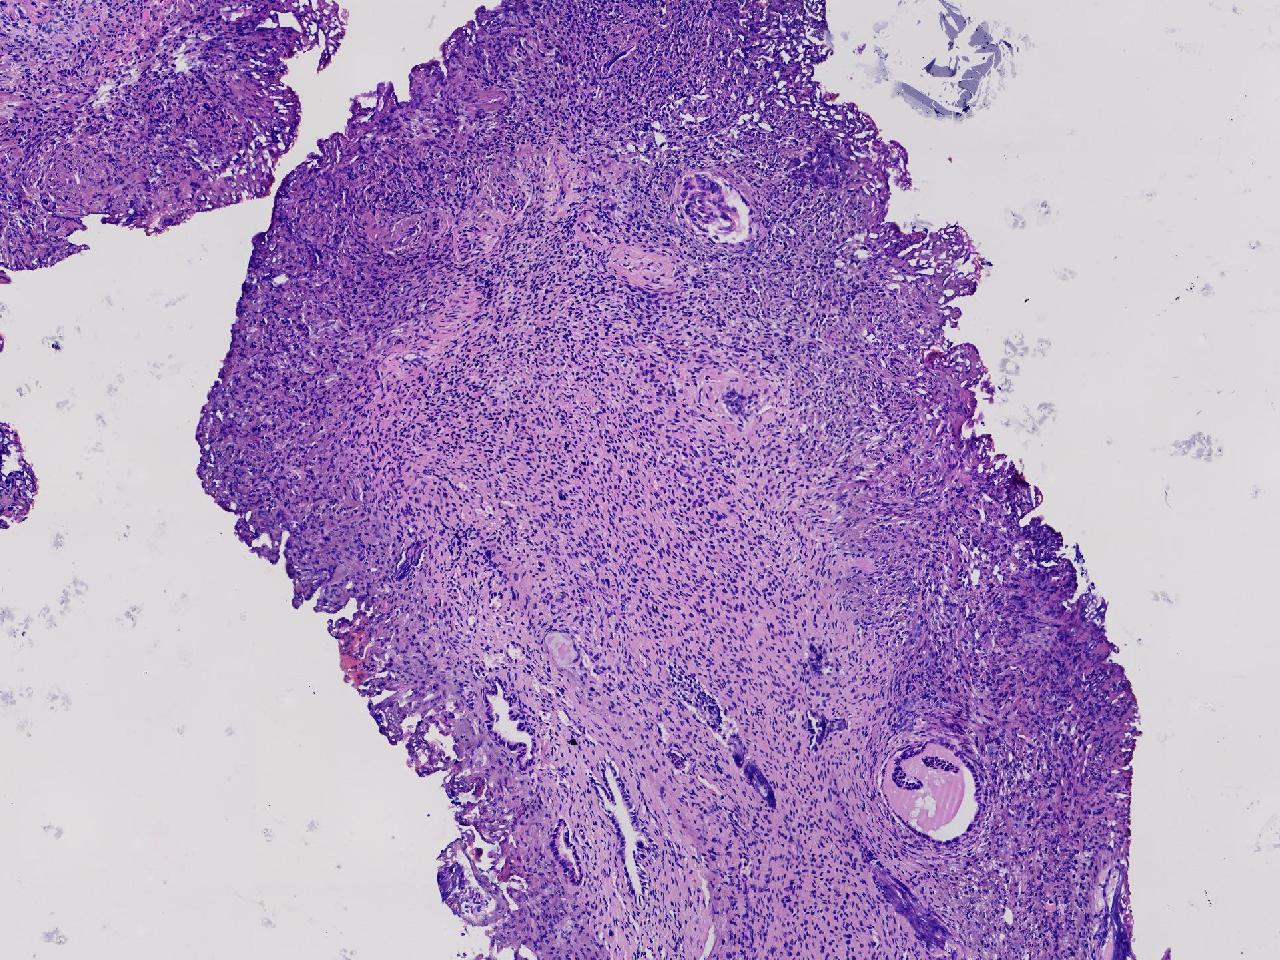

宫腔息肉?

性别

女

年龄

56岁

彩超示宫腔内见5x3ml的团状偏强回声结节,边界清。

灰粉色不整形软组织多块,0.5X0.3X0.3厘米。

首先考虑子宫内膜息肉,有些区域间质细胞较密,找找看有没有核分裂。

彩超提示强声团体积不小,待完整切除送检再综合诊断。